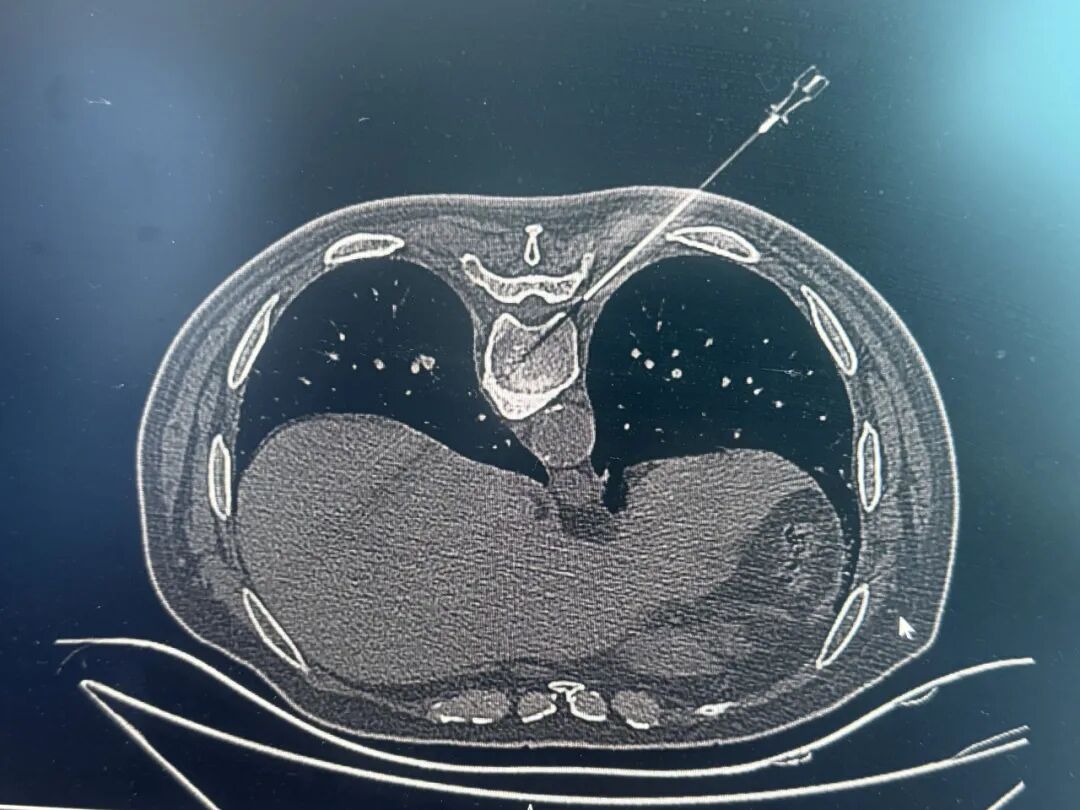

针对患者病情,朱杰为周某制定了详细的治疗计划,除传统的药物治疗(止痛、营养神经等对症治疗)、物理治疗外,还采取CT引导下射频消融术进行治疗。

CT引导下射频穿刺针顺利到靶点

CT引导下射频消融术是近年来快速发展起来的一种微创治疗手段,该技术借助CT精准定位,将0.5毫米的消融穿刺针直接作用在病变的神经根上,在解除神经压迫的同时不损伤周围组织,靶点直接定位在病变神经,可解除神经根压迫或刺激,缓解疼痛症状。